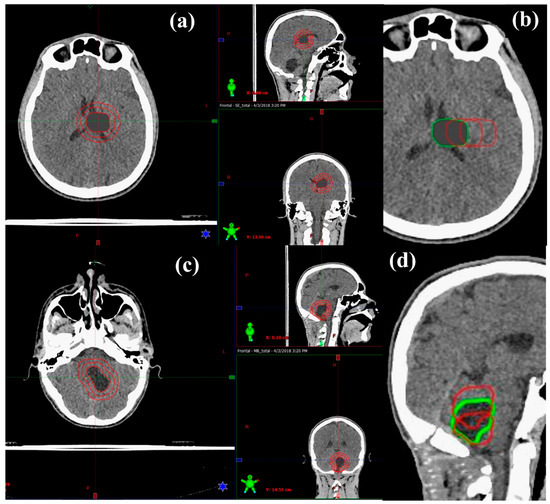

2.1. Patient Data and Target Volume Simulation

2.2. Treatment Planning

2.2.1. Prescribed Dose and Beam Arrangement for Intensity-Modulated Proton Therapy (IMPT)

2.2.2. Prescribed Dose and Beam Arrangement for Intensity-Modulated Photon Therapy (IMRT)